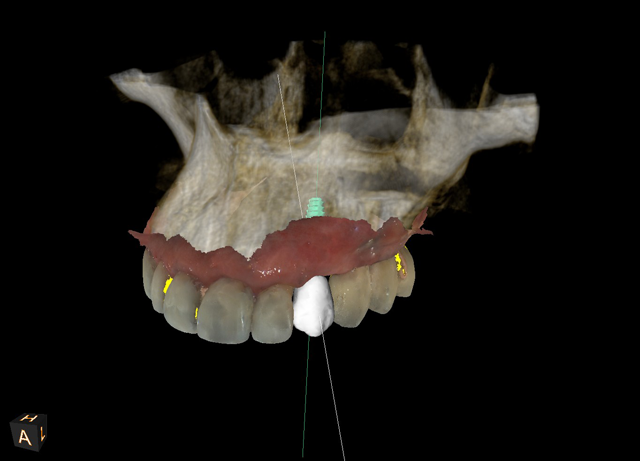

This technique starts with good diagnosis and treatment planning. Beginning with our clinical exam, we design our case with the end result in mind. A well-designed case, along with a well-designed provisional, will not only prepare the emergence profile prior to implant placement but will also assist the implant surgeon in choosing optimal implant position. When a cone beam computed tomography (CBCT) scan and a digital impression of the patient’s existing dentition are obtained, the goal is to create two files: the CBCT, which is a DICOM file, and the intraoral scanner file, which is in a STL format. We then merge those two files in an implant planning software to fabricate our guide and provisional restoration. If teeth are present, we can use these as guides to where we need to place our implants. If teeth are not present, then virtual teeth can be placed into the digital planning software so that implant position can be planned in an ideal location.

Typically, a surgical guide is printed next and temporary abutment and provisional restoration are milled from these digital files. This allows optimum implant placement as well as esthetic gingival contouring during the healing phase. We are starting to develop the emergence profile of the restoration to mimic that of a natural tooth by developing gingival contours through preplanned and pre-milled provisional restorations or gingival formers; inserted at the time of implant placement.

In this case, one file was sent to Roe Dental Labs in Ohio for fabrication of the surgical guide and another file was sent to Vulcan Dental Labs in Alabama for fabrication of a temporary restoration. The exactness of the digital technology allowed for this degree of specificity whereby both the guide and the temporary fit together as if they were made at the same lab (Figs. 6 and 7).